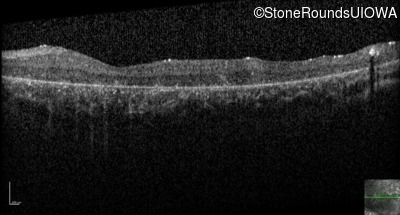

Optical Coherence Tomography - Right - 5/200

Exemplar / OCT Stack